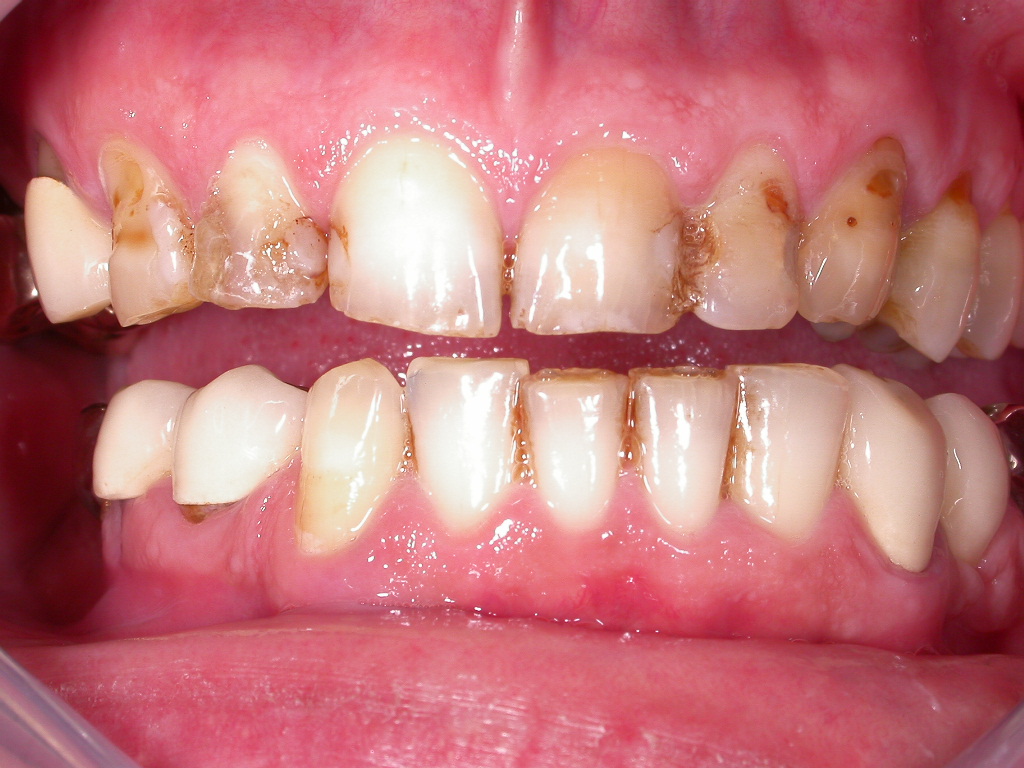

Sehr unzufriedener Patient, der immer wieder Reparaturen mit Kunststoff und einzelnen Kronen bei seinem langjährigen Zahnarzt bekommen hat

Vorher: Sehr unzufriedener Patient, der immer wieder Reparaturen mit Kunststoff und einzelnen Kronen bei seinem langjährigen Zahnarzt bekommen hat

Kompletterneuerung mit vollkeramischen Veneers und Kronen; vorher Endo-Revisionen unter dem Mikroskop und PAR-Behandlung; Entfernung der Weisheitszähne in unserer Praxis

Nachher: Kompletterneuerung mit vollkeramischen Veneers und Kronen; vorher Endo-Revisionen unter dem Mikroskop und PAR-Behandlung; Entfernung der Weisheitszähne in unserer Praxis